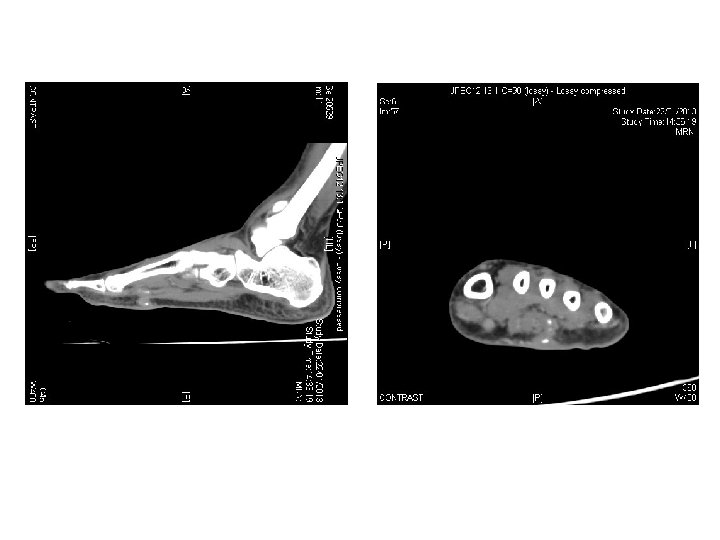

Case 2 • • • M/42 Hx of stepping to nail Left sole wound

Case 2 • • • M/42 Hx of stepping to nail Left sole wound unhealed for 6 months P/E: 4 mm size ulcer in left sole, discharge +ve X ray left foot was taken

Questions • What was the X ray finding • What you were suspected? •

Questions • What was the X ray finding • What you were suspected? • What further investigations you would like to do to confirm the diagnosis?

• What did you think about the nature of material that caused the

• What did you think about the nature of material that caused the problem? (Metal, glass, plastic or wood) Why?

• What other investigation you would consider?

• What is your management?